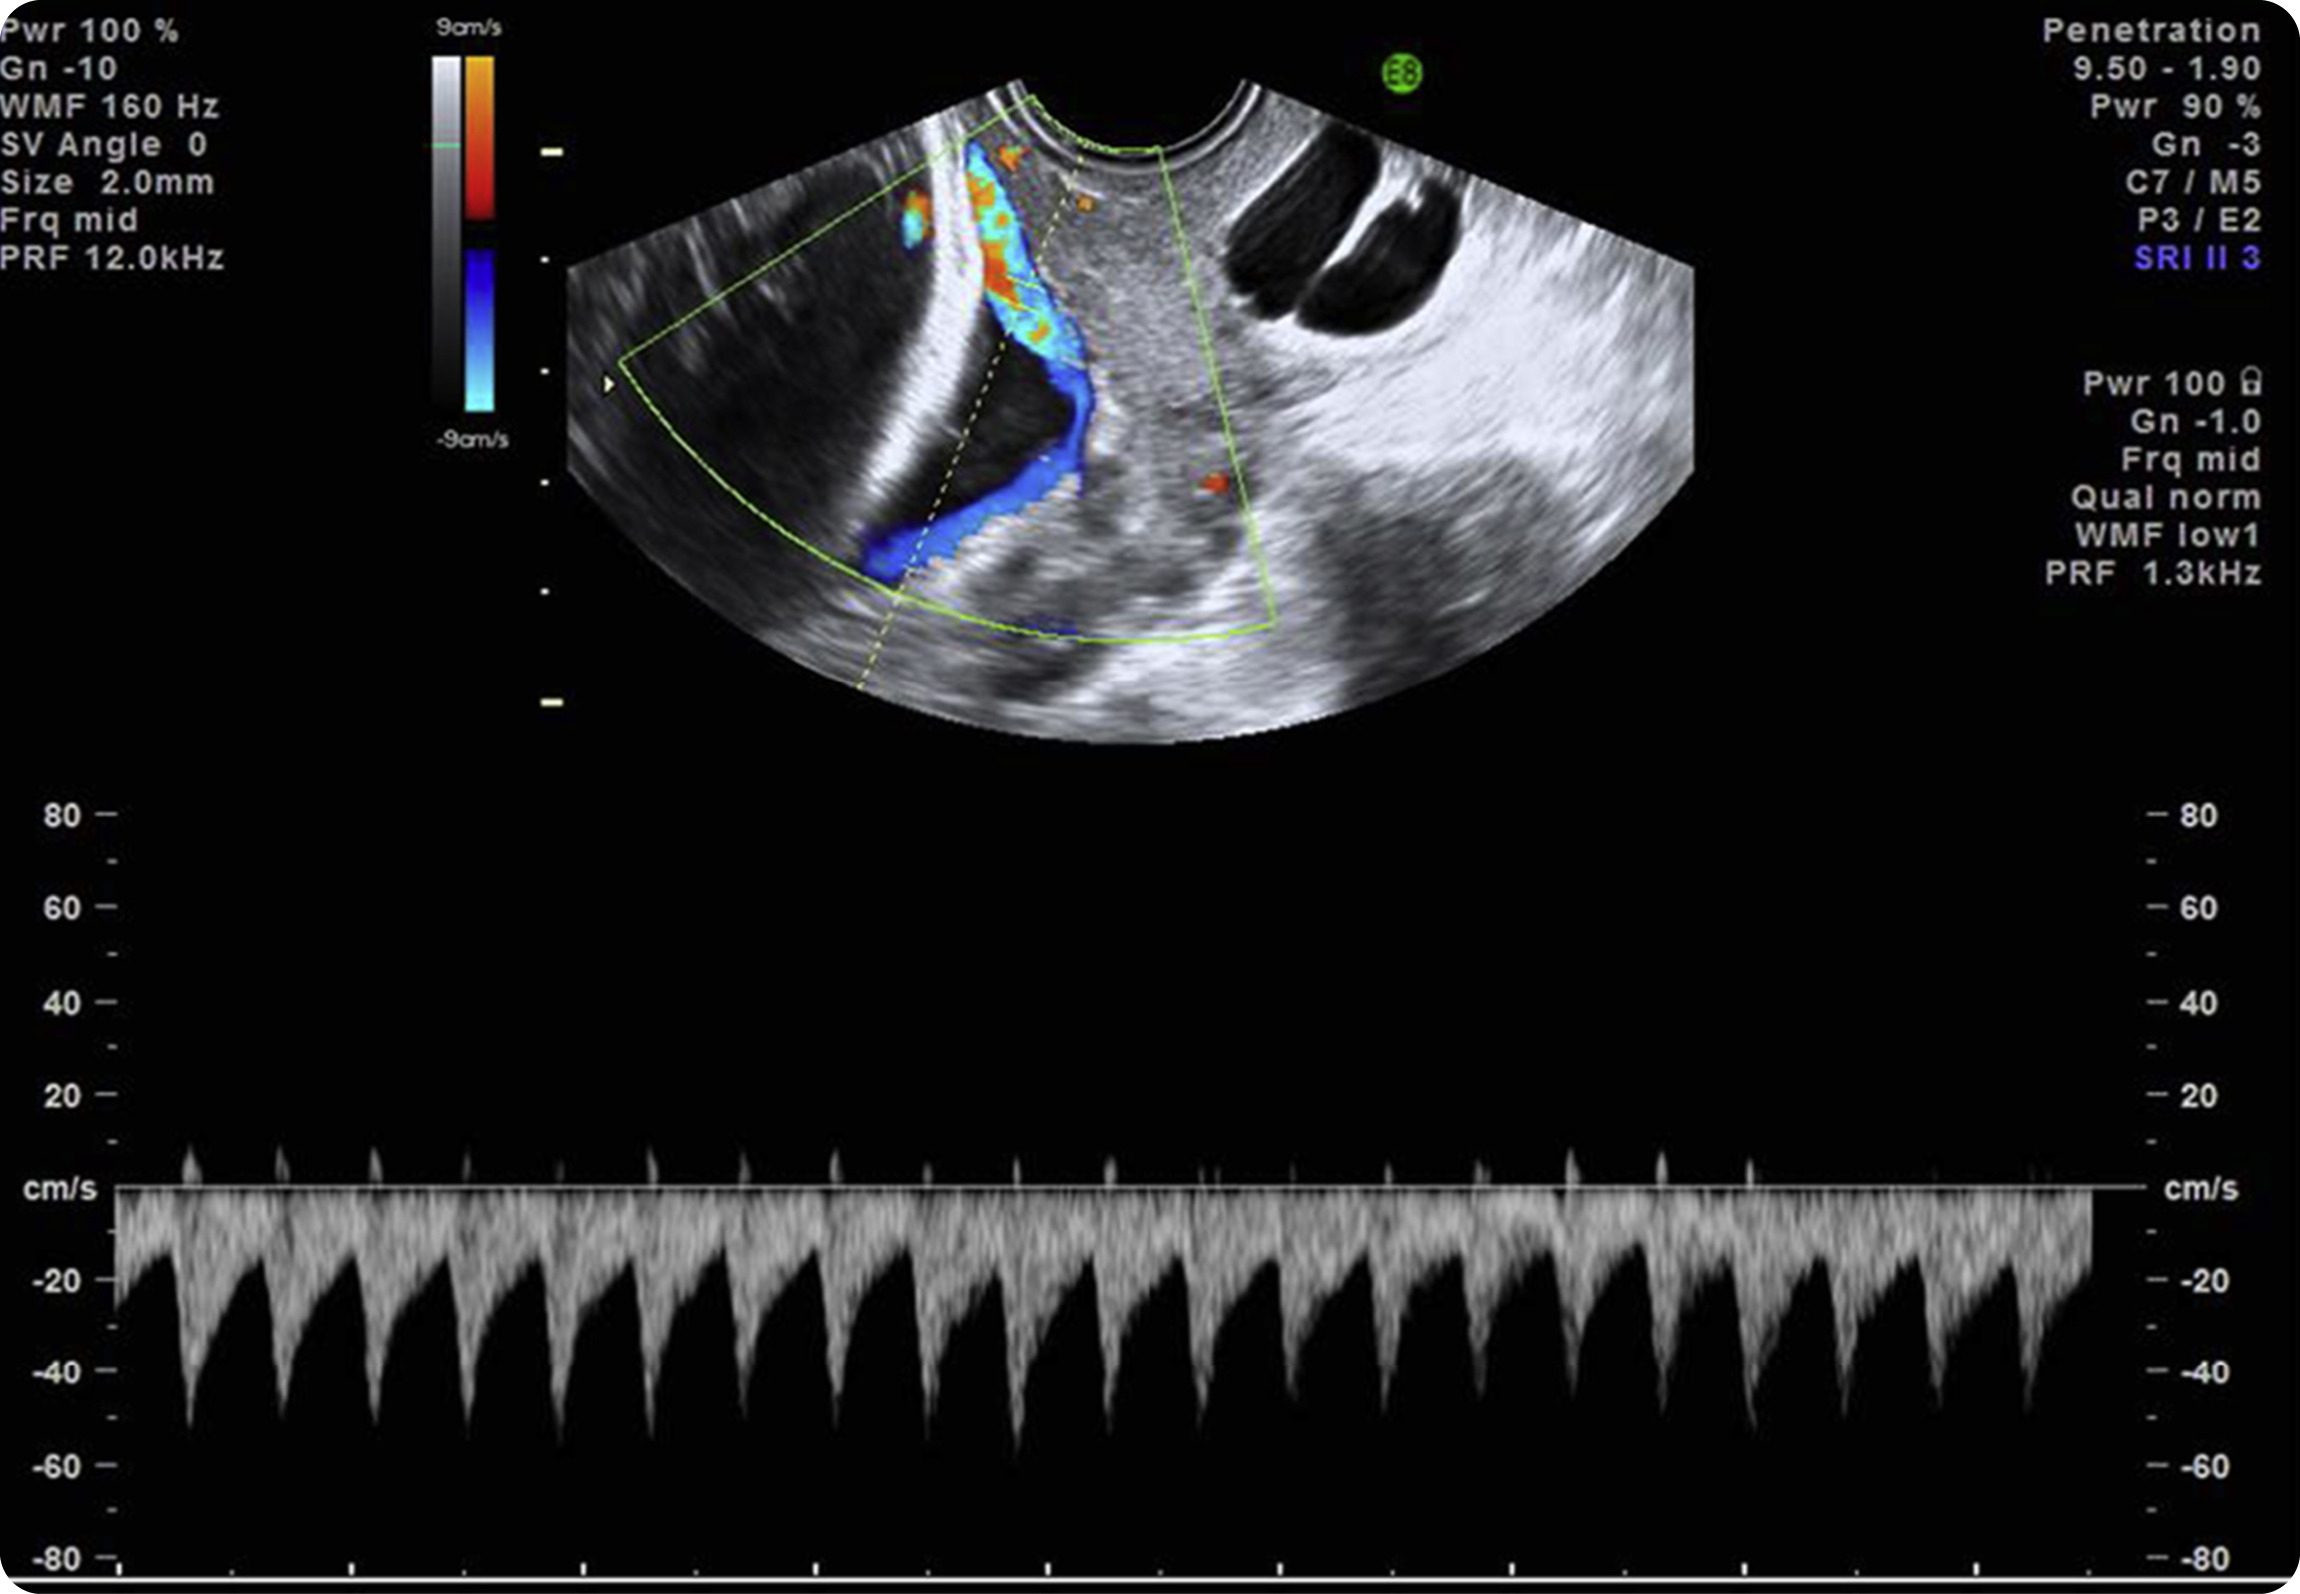

Figure 3. Transvaginal ultrasound scan with color Doppler image and pulsed wave Doppler image shows fetal heart rate

Pulsed wave Doppler of the vessel over the cervical os depicts a fetal heart rate, confirming a diagnosis of vasa previa.

Source: SMFM. Diagnosis and management of vasa previa. Am J Obstet Gynecol 2015.